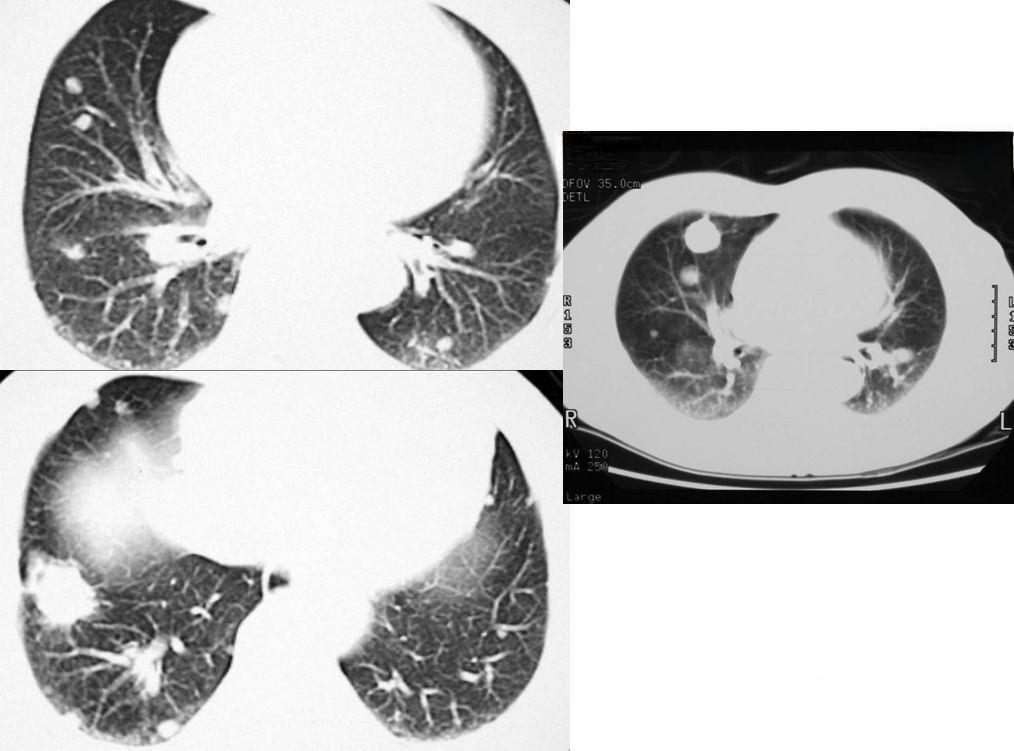

肺结核是全球第九大死因,其影像特点复杂多变,尤其是不典型肺结核的诊断更是充满挑战。传统的影像学诊断方法往往难以准确识别不典型病变,导致漏诊和误诊。近年来,人工智能技术的快速发展为这一难题带来了新的希望。

在不典型肺结核的诊断中,AI技术展现出独特优势。通过深度学习算法,AI系统能够识别和提取人眼难以察觉的微小特征,建立精准的诊断和鉴别诊断模型。例如,有研究使用纹理特征作为描述符,将胸部X线图像分类为结核和非结核,结果显示利用图像直方图中的统计特征可以有效检出肺结核。另一项研究提出了一种基于分段肺区域纹理特征的肺结核指数,结合决策树对胸部X线片进行分类,准确率高达94.9%。

AI辅助诊断不典型肺结核的具体方法主要包括:首先,使用图像分割算法对肺部扫描序列进行处理,生成肺部区域图;然后,根据肺部区域图生成肺部图像,并利用肺部分割生成的肺部区域图像和结节标准信息生成结节区域图像;接着,对基于卷积神经网络(CNN)的肺结节分割器进行训练,对图像进行肺结节分割,得到疑似肺结节区域;最后,使用3D CNN对肺结节进行分类,得到真正肺结节的位置和置信度。